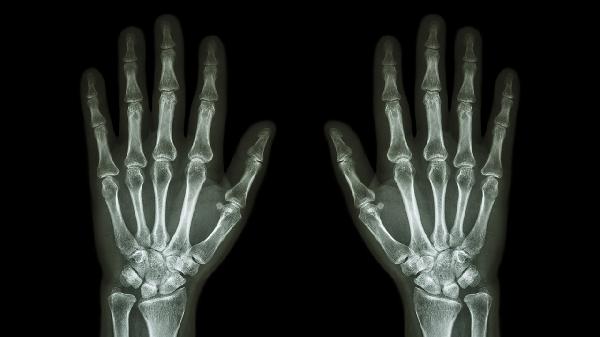

手指关节疼痛可遵医嘱使用布洛芬缓释胶囊、双氯芬酸钠缓释片、塞来昔布胶囊、硫酸氨基葡萄糖胶囊、甲氨蝶呤片等药物。手指关节疼痛可能与骨关节炎、类风湿关节炎、痛风性关节炎、外伤或腱鞘炎等因素有关,建议及时就医明确病因后用药。